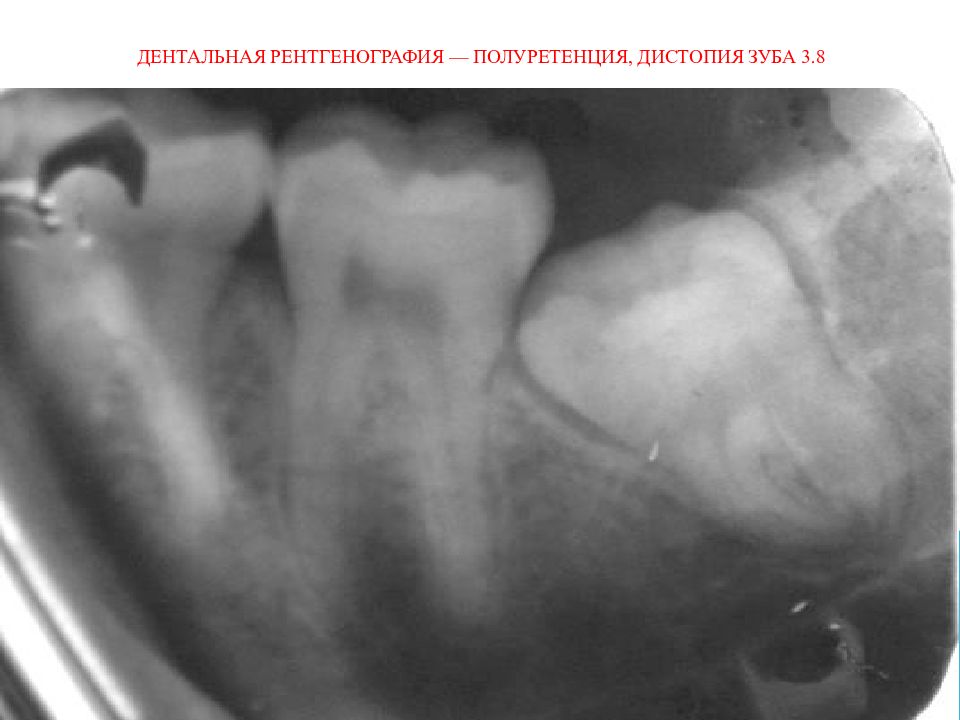

• Дентальная рентгенография — полуретенция, дистопия зуба 3.8

Для постановки диагноза и составления плана лечения используются следующие лучевые методы исследования: 1) дентальная рентгенография 2) боковая рентгенография нижней челюсти со стороны локализации патологического процесса; 3) ортопантомография 4) спиральная компьютерная томография; 5) конусно-лучевая компьютерная томография

Слайд 22: Дентальная рентгенография — полуретенция, дистопия зуба 3.8